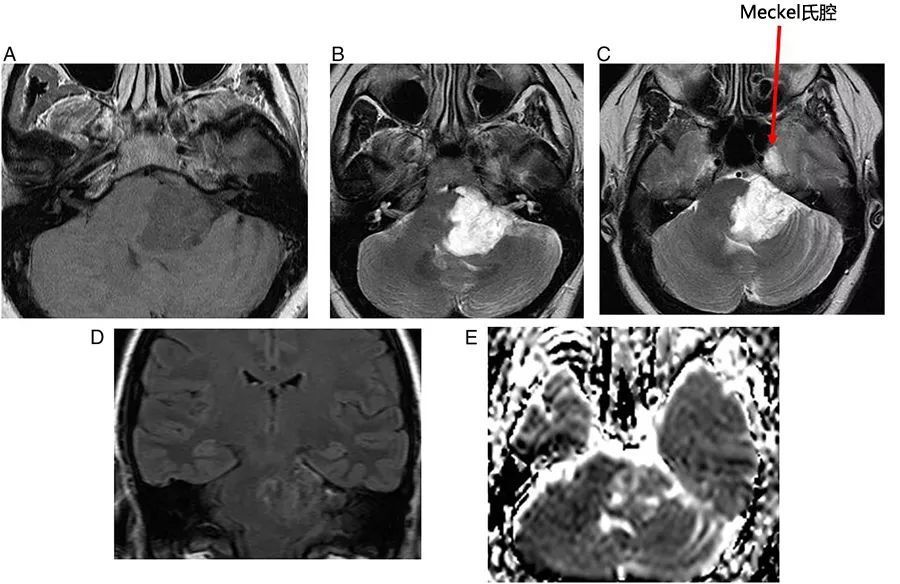

图6  左侧桥小脑角区表皮样囊肿。病灶呈T1低信号、T2高信号,DWI上弥散受限,延伸至Meckel氏腔,左侧小脑中脚和第四脑室受压,三叉神经、面神经、听神经也被压缩